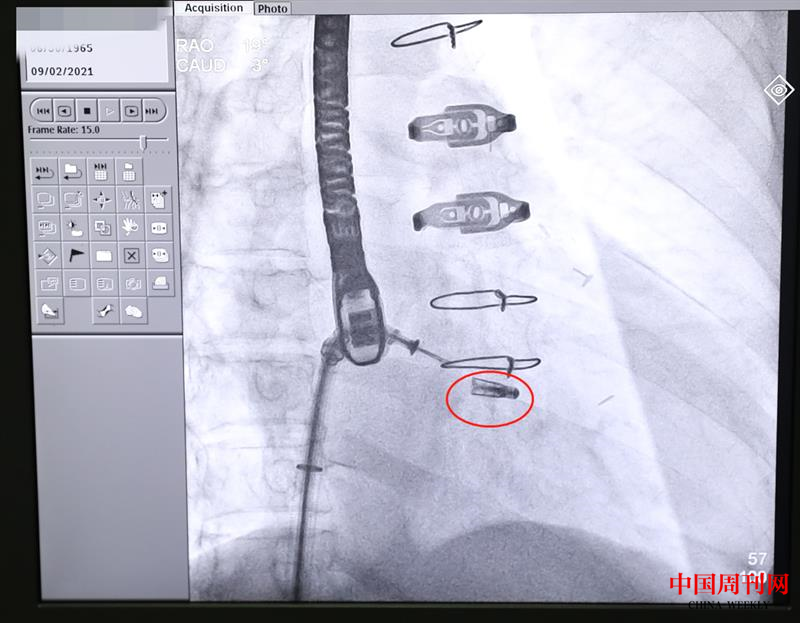

9月2日上午,在完成充分的术前准备和预案工作后,中大医院心血管内科、麻醉科、胸心外科等组成联合保障团队。在麻醉科医生成功实施全麻后,心血管内科马根山主任医师、丁建东主任医师、陈立娟主任医师、徐荣丰主治医师等开始施行介入手术,在食道超声和医学影像设备的引导下,手术专家经皮穿刺,借助先进的微创导管输送系统,通过逐级扩张鞘将可操控导引导管送入左心房,引导二尖瓣夹导管输送系统进入左心房;接着在左心房调整二尖瓣夹的位置。由于该患者病变复杂,二尖瓣夹闭的难度很大,相当于患者的二尖瓣上有个大口子,需要用一个夹子把二尖瓣的前瓣和后瓣夹起来,达到减轻反流的目。介入专家团队在手术过程中反复调整、多次探讨,最终成功夹合前后瓣的部分瓣叶,使之贴合在一起。经超声及医学影像造影检查证实,二尖瓣夹已夹紧,患者反流症状明显减轻,最终释放夹子,撤回输送系统,完成修复手术。术后,张先生的症状显著改善,目前,正在接受进一步观察治疗。